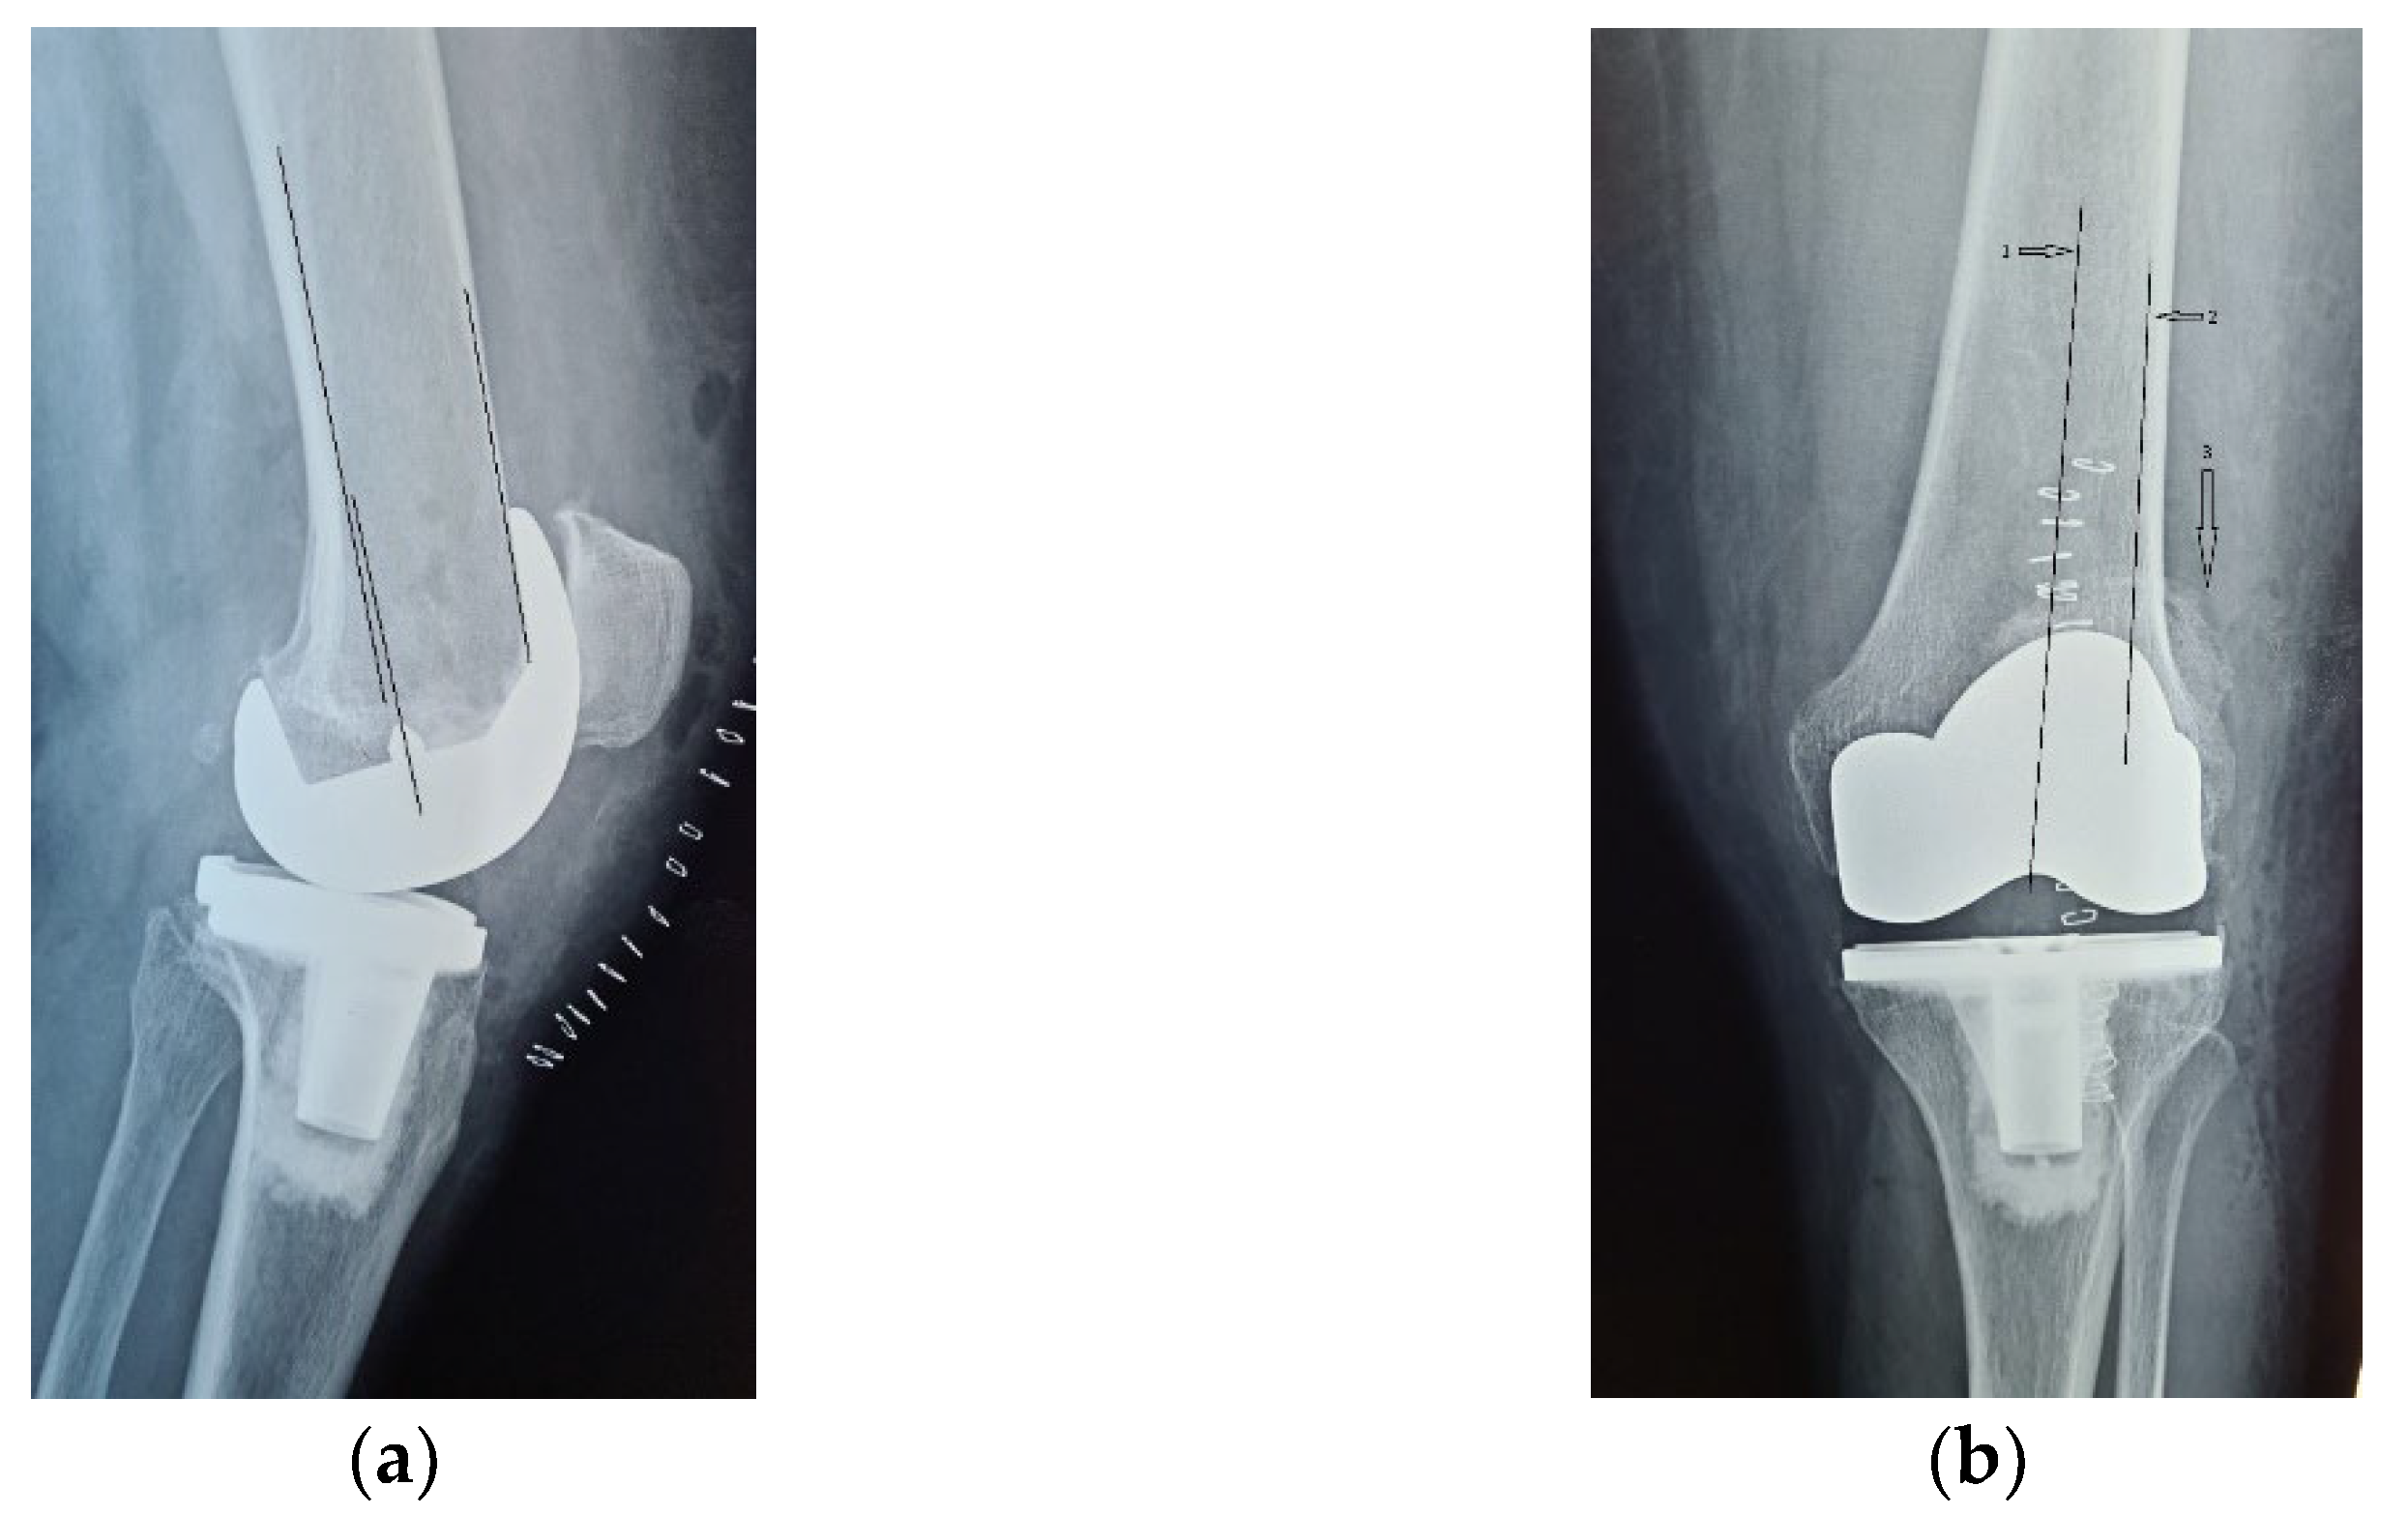

Alongside with the clinical scores, the patient was also evaluated radiologically, with CT scans and standard X-rays. Radiological investigations, using coronal, lateral and axial views (Merchant view) showed patellar arthrosis and a slight lateral subluxation of the patella (Figure 4).

Figure 4.

(a) coronal view, patellar lateral subluxation (arrow) compared to femoral axis with (1) marking the femoral trochlear axis, (2) patellar axis and (3) the patella must be centered in the femoral trochlea; (b) lateral view, patellar wear, patellar trochlea deformation and subchondral bone condensation with (4) marking subchondral osteocondensation and (5) patella bone deformation; (c) axial view, patellar lateral subluxation, and deformation, osteocondesation of the subchondral bone with (6) patella bone deformation and condensation, (7) femoral trochlear axis and (8) Patellar axis.

CT images, subject to artifacts generated by the implant, show patellar wear and peripatellar inflammatory phenomena (Figure 5).

Figure 5.

CT images: (a) Sagittal view showing patellar arthrosis, condensation of subchondral bone. (b) Axial view showing patellar arthrosis, deformation, and lateral subluxation (arrow) with (1) marking the femoral trochlear axis and (2) patellar axis; (c,d) CT 3D image, peripatellar inflammation.